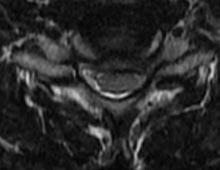

50 year old man presenting with left biceps and triceps weakness with numbness in his hand.

C6 corpectomy with complete resolution of the weakness and numbness.